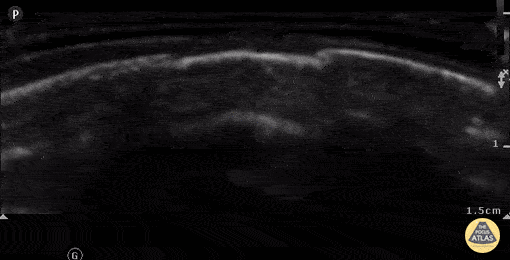

7 week old with left parietal skull fracture. Note irregular edges on both sides and slightly depressed bony cortex. Contributor: Antonio Riera, MD